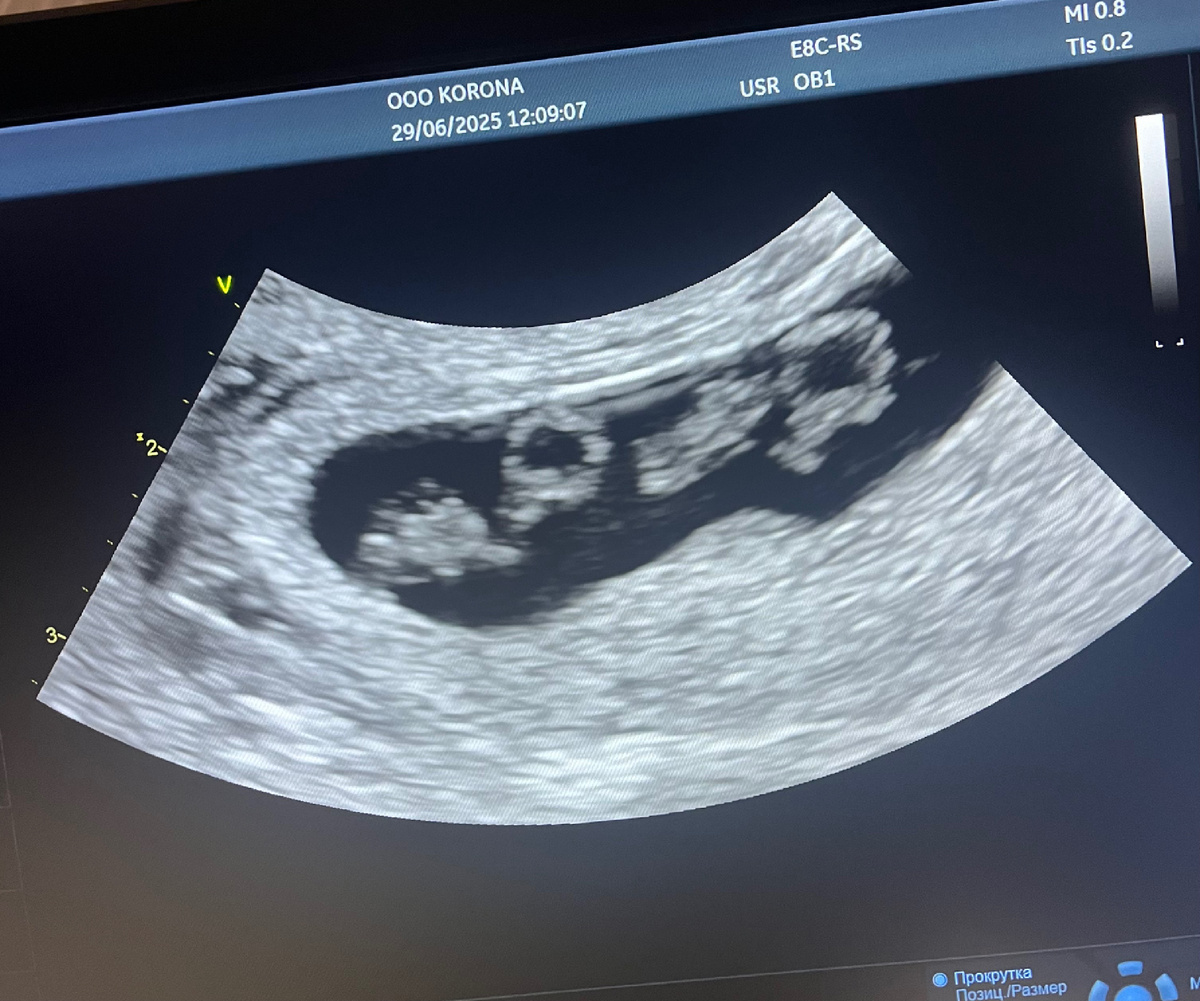

На 8-й неделе пришла пора первого УЗИ. Помню, как лежала на кушетке, болтая ногами, и шутила с мужем: «Давай поспорим, мальчик или девочка?»

А потом… тишина. Врач молчала, водя датчиком по животу. Я испугалась: «С ним всё в порядке?». Она не ответила, только сделала несколько снимков с разных ракурсов.

— Ольга, вы не думали, что их может быть двое? — спросила она наконец.

— Кто? — не поняла я.

— Ваши дети. Вот сердцебиение первого, а вот — второго.

На экране мелькали два крошечных сердца, два комочка, которые толкались в разные стороны. Я схватила руку мужа и вцепилась в неё, будто боялась, что он исчезнет. Слёзы катились сами - смесь шока, страха и невероятной радости. *

«Два? Но как?» повторяла я, пока врач улыбалась: «Бывает!».